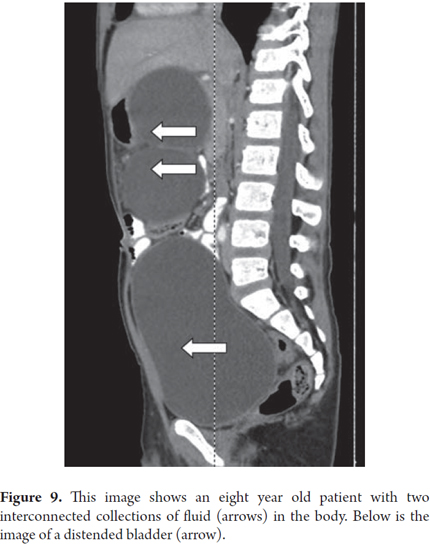

Case 9

Two months after an eight year old child had spent three weeks in the intensive care unit with medical treatment for blunt abdominal trauma and severe acute pancreatitis, the patient continued to suffer from early satiety and abdominal pain. A CT scan showed two giant connected 121mm collections of fluid in the head and body of the pancreas (Figure 9). Transgastric endoscopic ultrasound (EU) guided drainage was performed through placement of a single 10 Fr pigtail prosthesis. The child's development was very good, and a follow-up CT scan showed no evidence of the lesion after 3 months (Figure 10). The prosthesis was removed. After 6 months of follow up there had been no recurrence and the patient continues to be asymptomatic.